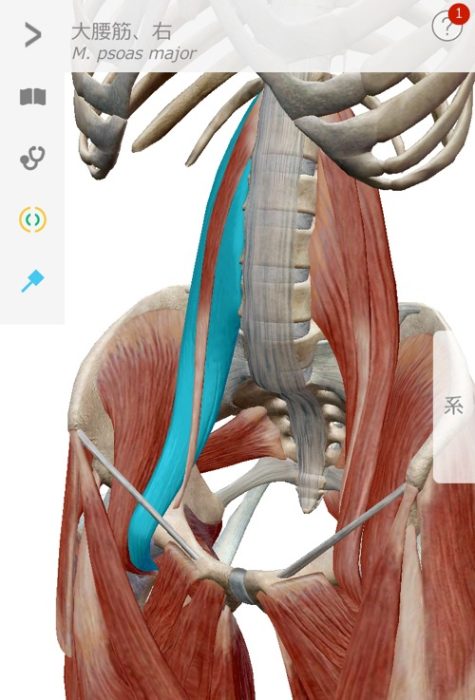

大腰筋が腰椎を圧迫

僕の経験による腰椎椎間板ヘルニアの本当の原因は大腰筋にあります。

この大腰筋ですが

主な役割:股関節を安定させる、歩く際に脚を挙げる働きをします。

起始停止:起始部は胸椎(T12)から腰椎(L1~5)の横突起で、大腿骨の小転子に停止します。

となっております。

つまり足の付け根部分と腰椎を結んでいる筋肉なのです。

腰椎椎間板ヘルニアが大腰筋の硬直等により発症するメカニズ�

硬直した大腿部が大腰筋を下方向に引っ張ったり、大腿骨頭の位置ずれが起きて大腰筋が下方向へ強く引っ張られたり、大腰筋そのものが硬直した場合に 起始部として付着している腰椎1〜5の何れかに負荷をかけてしまい圧迫が起き、押しつぶされた軟骨が変形したり 飛び出したりするのではないか?とい仮説を元に大腰筋を補正する施術をした結果98%もの方々の痛みが消失しただけでなく、飛び出していた軟骨も元に戻ったのです。

大腰筋が下方向に圧力をかけ椎間板が変形や飛び出しを起こす。

まずはこちらの図。大腰筋ですがこのように腰椎から足の付け根部分に接続されていますので、長時間座っていたり、立ち仕事の長い方、立ったりしゃがんだりを繰り返す方には負担が大きく硬直して縮むことで腰骨を足の方へ(下方向)引っ張ると先程説明しました。

大腰筋が硬直

硬直した腰筋が縮んで腰椎を下方へ圧迫